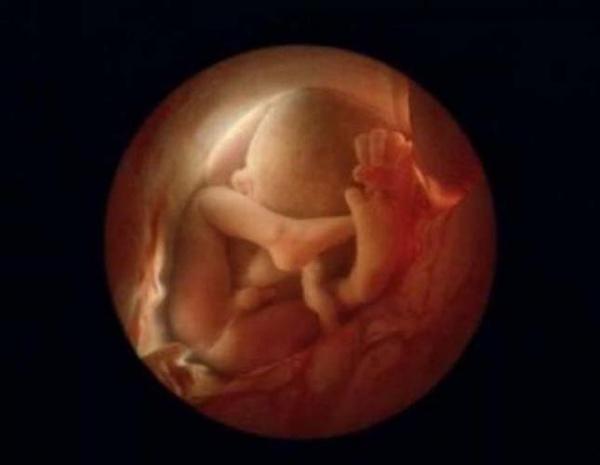

24 εβδομάδων

6 μηνών

36 εβδομάδων. Σε έναν μήνα το μωρό θα γεννηθεί